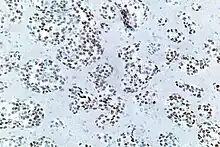

Thyroid transcription factor-1 (TTF-1) is a protein that regulates transcription of genes specific for the thyroid, lung, and diencephalon. It is also known as thyroid specific enhancer binding protein. It is used in anatomic pathology as a marker to determine if a tumor arises from the lung or thyroid. NKX2.1 can be induced by activin A via SMAD2 signaling in a human embryonic stem cell differentiation model.[7]

TTF-1 positive cells are found in the lung as type II pneumocytes and club cells. In the thyroid, follicular and parafollicular cells are also positive for TTF-1.

For lung cancers, adenocarcinomas are usually positive, while squamous cell carcinomas and large cell carcinomas are rarely positive. Small cell carcinomas (of any primary site) are usually positive. TTF1 is more than merely a clinical marker of lung adenocarcinoma. It plays an active role in sustaining lung cancer cells in view of the experimental observation that it is mutated in lung cancer.[11][12][13][14]

However others have found that TTF-1 staining is often positive in pulmonary adenocarcinomas, large cell carcinomas, small-cell lung carcinomas, neuroendocrine tumors other than small-cell lung carcinomas and extrapulmonary small-cell carcinomas.[16]

- Image by Mikael Häggström, MD. Source for significance: Bejarano PA, Mousavi F (2003). "Incidence and significance of cytoplasmic thyroid transcription factor-1 immunoreactivity". Arch Pathol Lab Med. 127 (2): 193–5. doi:10.5858/2003-127-193-IASOCT. PMID 12562233.